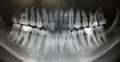

Мне 26 лет, с детства волновал вопрос кривых зубов. Зубы очень слабые и постоянно подвергаются заболеванию кариесом, в следствии чего, почти каждый зуб с пломбой.

Возможно ли выровнять такие зубы, если зуб, который во втором ряду, и передний правый резец мёртвые? Фото прилагаю. И если да, то не повредятся ли, и не отпадут ли пломбы при установке и в процессе выравнивания?

Конечно, причина постоянного образования кариеса — это скученность зубов. Естественно, Вам требуется именно ортодонтическое лечение.